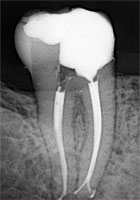

Примеры хорошо запломбированных каналов:

При лечении в одно посещение, зуб сразу восстанавливают пломбой. При лечении в два-три посещения полость зуба сначала закрывается временной пломбой, а в последнее посещение временную пломбу заменяют на постоянную.